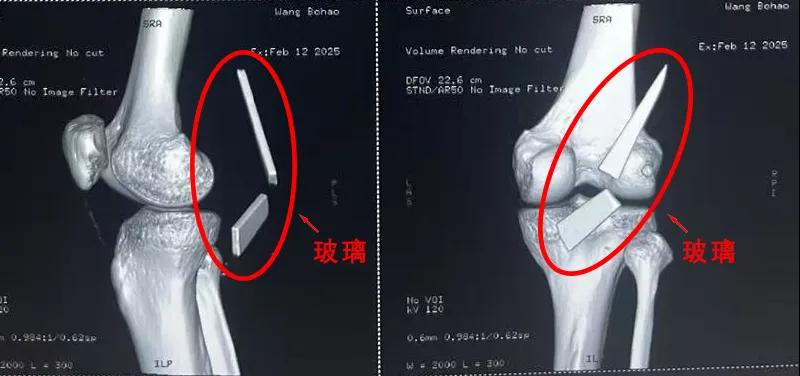

患者家屬這才開始意識到問題的嚴重性,便帶著孩子到鄉(xiāng)鎮(zhèn)衛(wèi)生院檢查——結果顯示右膝關節(jié)后方竟然殘留著兩塊兒鋒利的碎玻璃,測量后預估玻璃總長將近13厘米!

由于玻璃位置毗鄰坐骨神經和股動脈,一旦刺破股動脈,將嚴重威脅生命。家屬著急萬分,想著能否盡快手術取出碎片,于是慕名來到漯河醫(yī)專二附院(漯河市骨科醫(yī)院、漯河市立醫(yī)院)手顯微外科(修復重建骨感染科)。

術中,馬廣輝醫(yī)生憑借扎實的理論知識和嫻熟的顯微外科技術,順利找到深深刺進肌肉的兩塊玻璃,肉眼可見玻璃尖端距股動脈僅有不到半公分的距離!如果患者再耽誤半天或者再多活動幾次膝關節(jié),小指粗的股動脈很有可能被玻璃扎破,后果難以想象。

最終,馬廣輝醫(yī)生在血管、神經表面順利取出兩塊玻璃碎片,拆除了埋在患者膝關節(jié)的“炸彈”。在告知患者家屬術中情況后,家屬懸著的心終于放了下來。